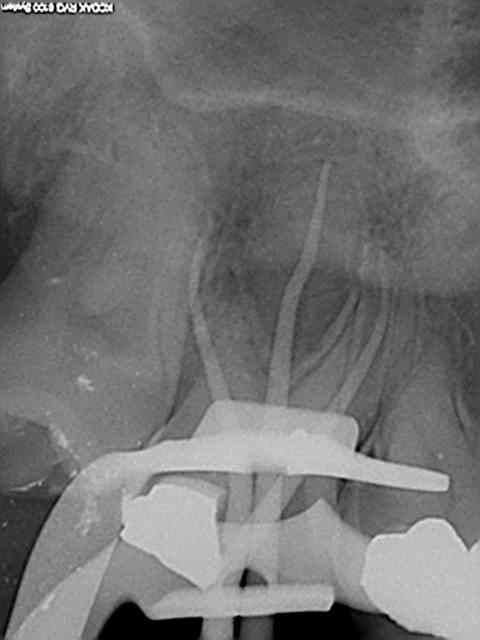

90 mn 2 molar endo + extrac 38. Un peu lent du à la difficulté à anesthésier (30 mn). les crochets apicaux traités comme si ils n'existaient pas avec le r25.

les 6 canaux avec le même r25. Attention toutefois je m'y suis repris à plusieurs reprises pour envoyer le s1 à l'apex (alternance r25 s1) et une bonne ouverture des entrées au largo ainsi qu'une très large cavité d'accès. Je n'ai à ce jour jamais cassé de r25, mais jamais essayé avec les plots en plastique .)

cela n'était pas des petites racines lt 24-25 mm. Big up à la digue qui m'a apporté un très gros confort de travail et m'a fait gagner du temps. Il n'y a que les imbéciles qui ne changent pas d'avis.